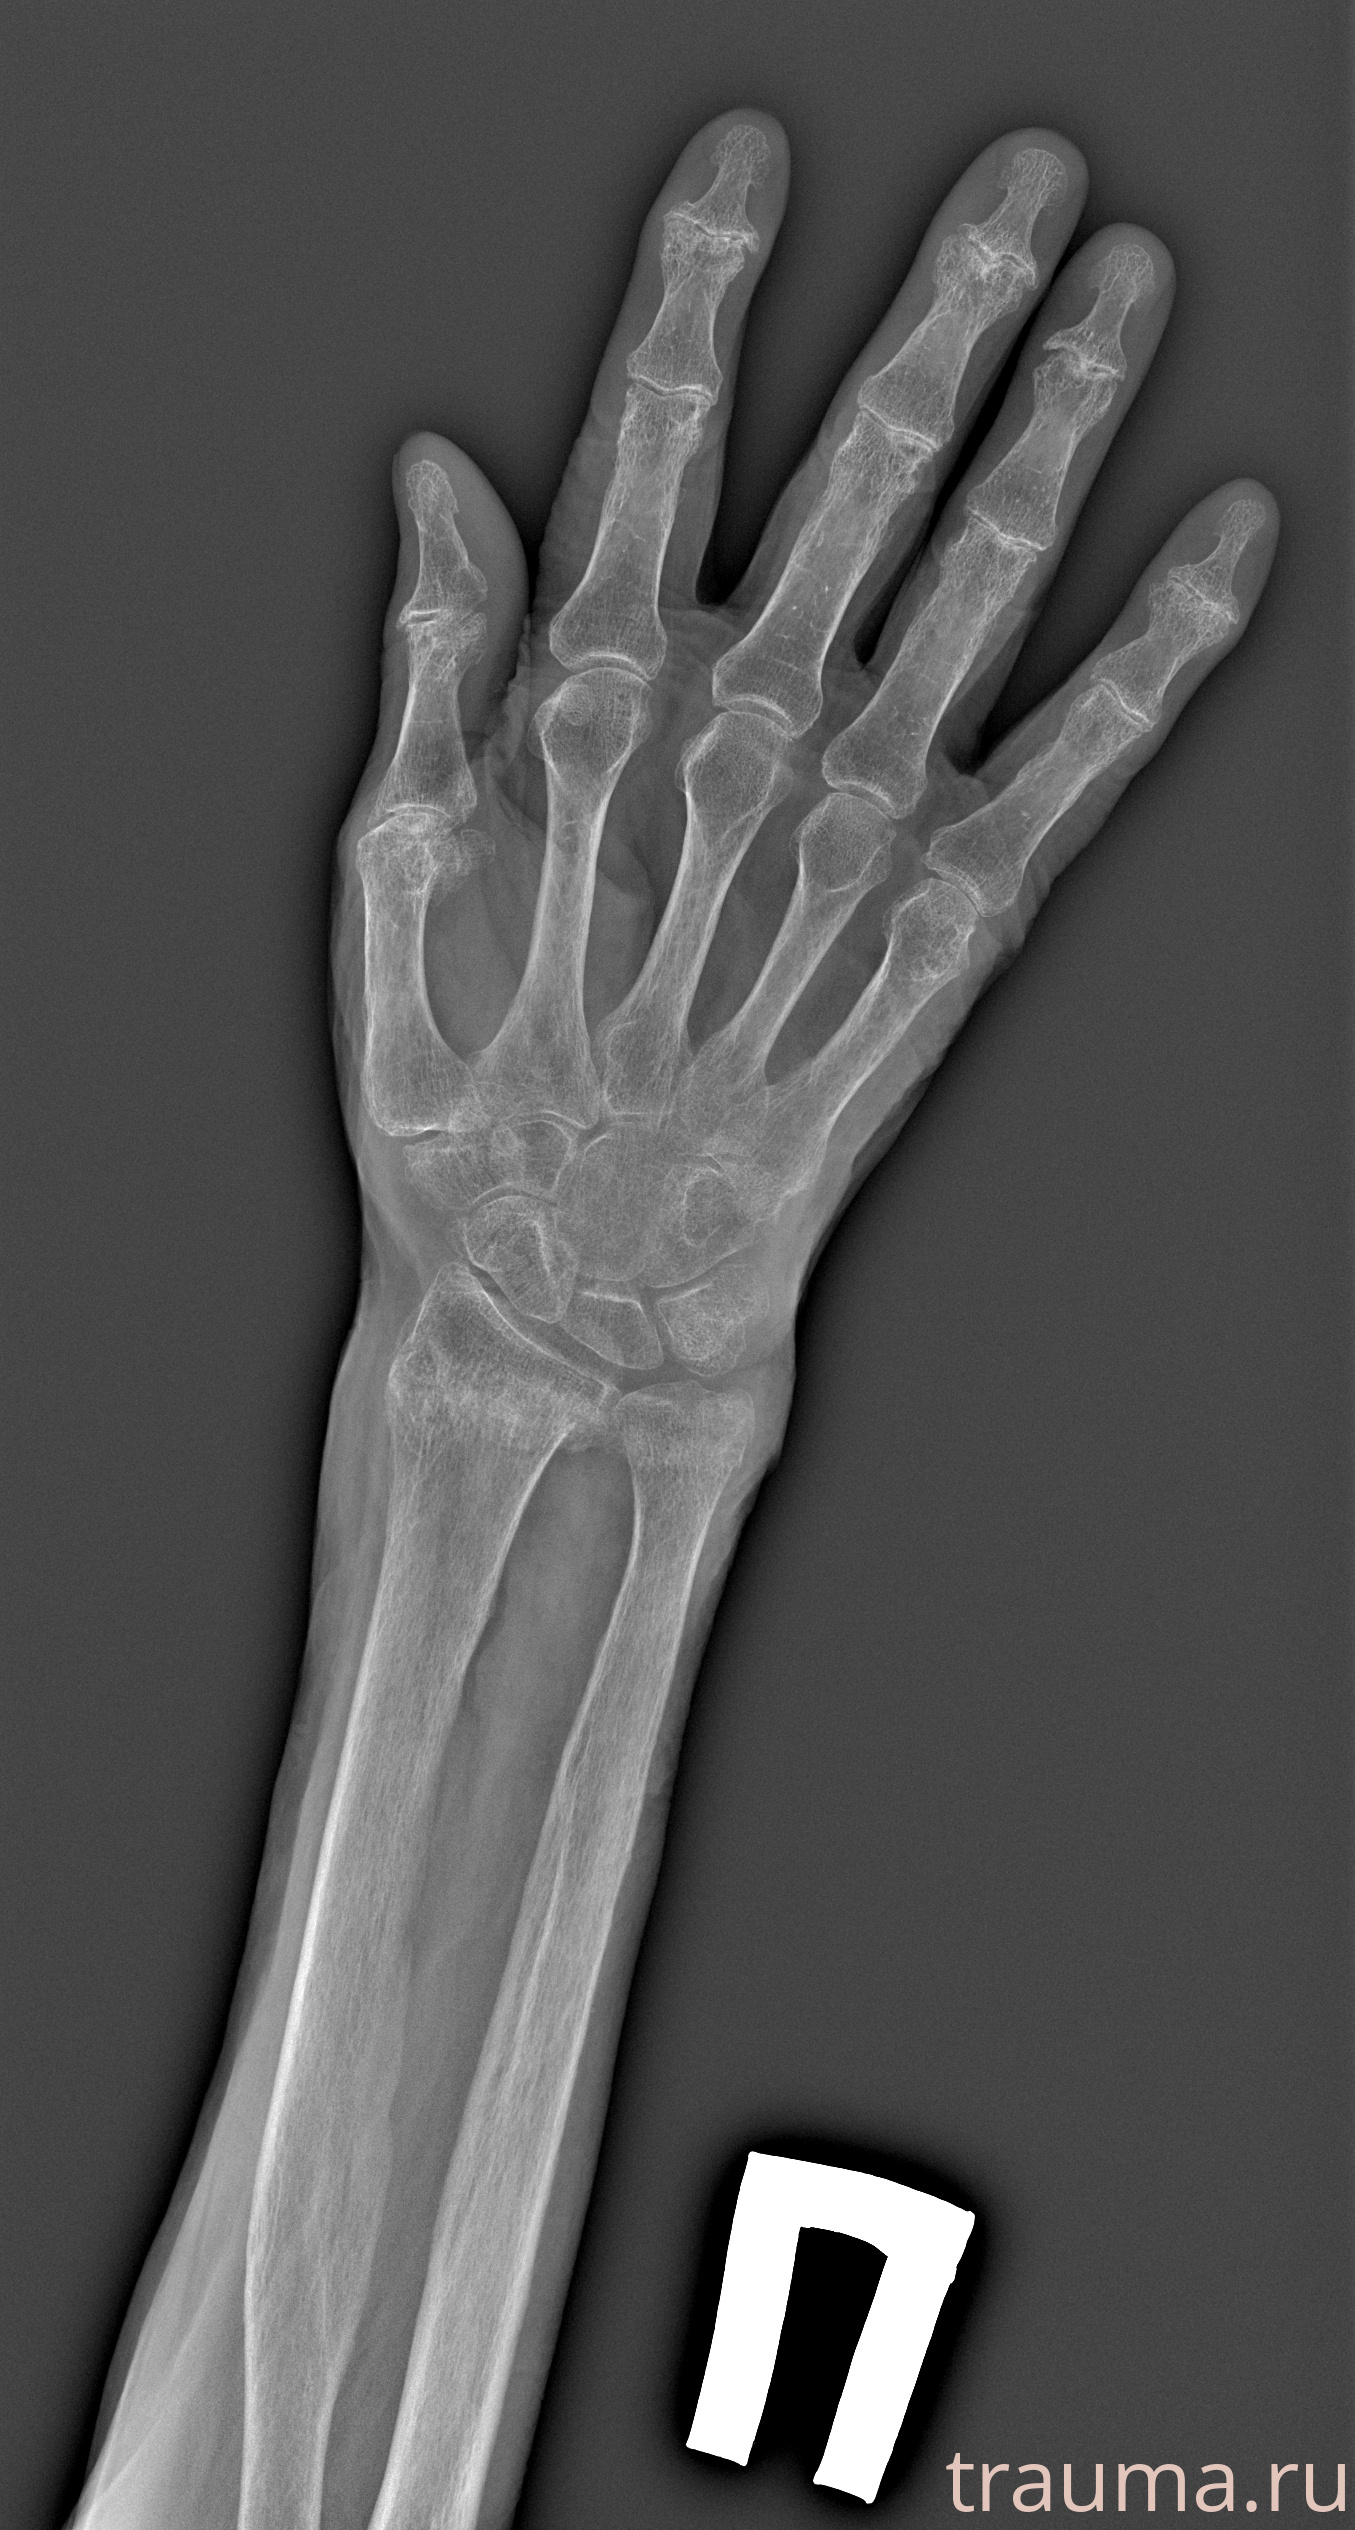

Перелом 3-5 ребер слева